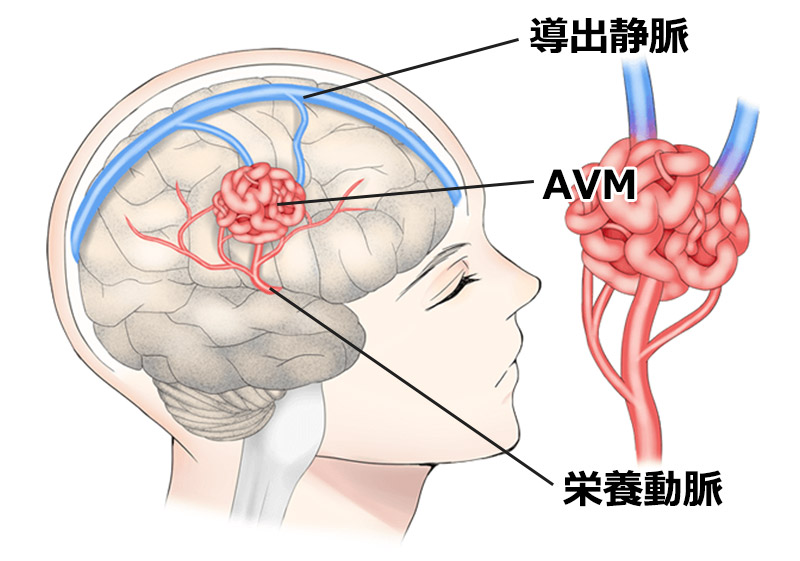

動静脈奇形がある場合、動脈は毛細血管を通さずに静脈と直接つながっているため、長時間動脈の血圧を支えることができず、静脈が破裂してしまいます。

この 2 つの間の異常な伝達はフィステルと呼ばれ、AVM 内に 1 つ以上存在する場合があります。

ブラジル神経放射線診断治療学会によると、動静脈奇形がなぜ起こるのか正確にはわかっていないが、最も論理的な説明は、神経系の血管の発達に異常があり、動脈毛細血管と毒毛細血管の損傷を引き起こすということだろう。結合し、静脈と動脈の間に直接通信を引き起こします。

奇形動脈は太く拡張しており、血液循環が速いため、脳出血を起こすことがよくあります。

血液を排出する静脈も AVM プロセスによって拡張 (静脈瘤の出現) を受ける可能性があり、症例の 15% で動脈瘤が形成されます。どちらも脳出血を引き起こす可能性があります。